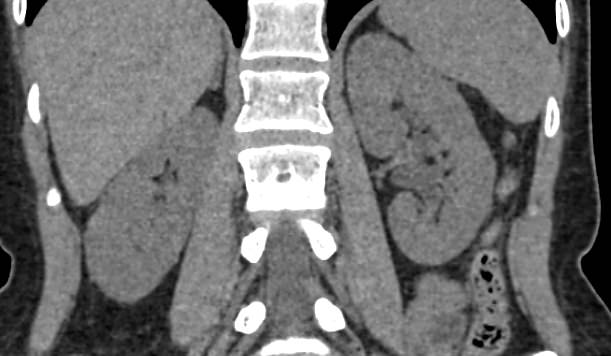

МСКТ почек и мочевыводящих путей с контрастированием позволяет выявить опухолевые образования на ранних стадиях, отличить доброкачественную опухоль от злокачественной, определить размеры опухоли, точную локализацию и степень распространения в окружающие ткани. Компьютерная томография почек с внутривенным болюсным контрастированием необходима для определения тактики лечения и объема оперативного вмешательства.

- оценке плотности конкрементов почек перед процедурой дробления;

- диагностике новообразований и метастазов;

- контроле состояния почек после операций;

- определении участка для взятия биопсии;

- выявление сосудисто-мочеточникового конфликта